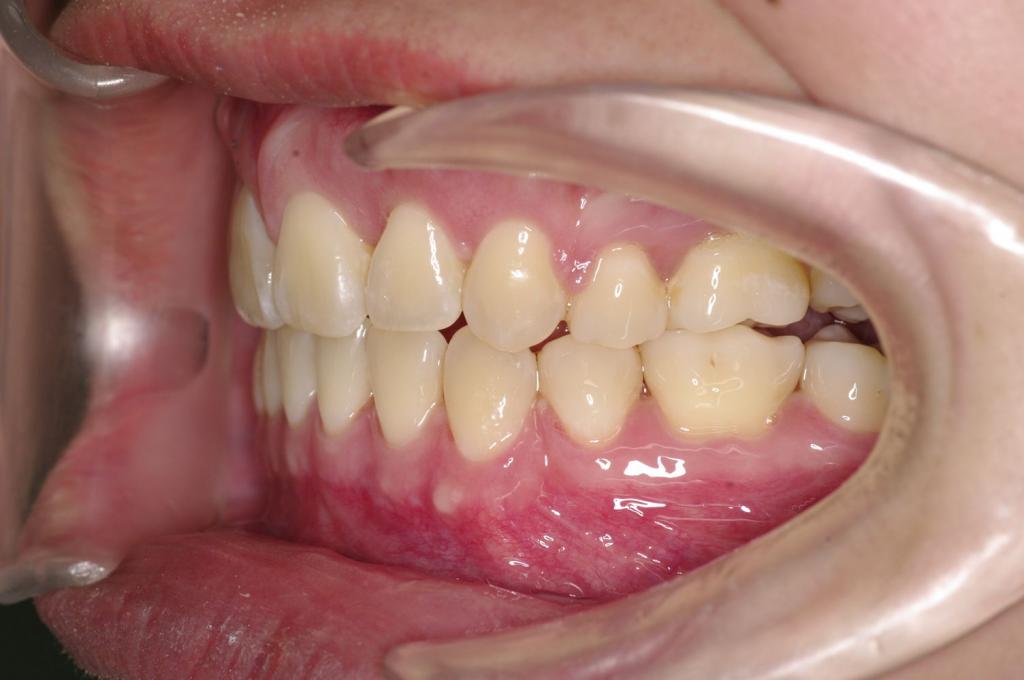

前歯、出っ歯・開咬の矯正治療

(治療期間、治療前後写真、治療方法、費用)WORKS